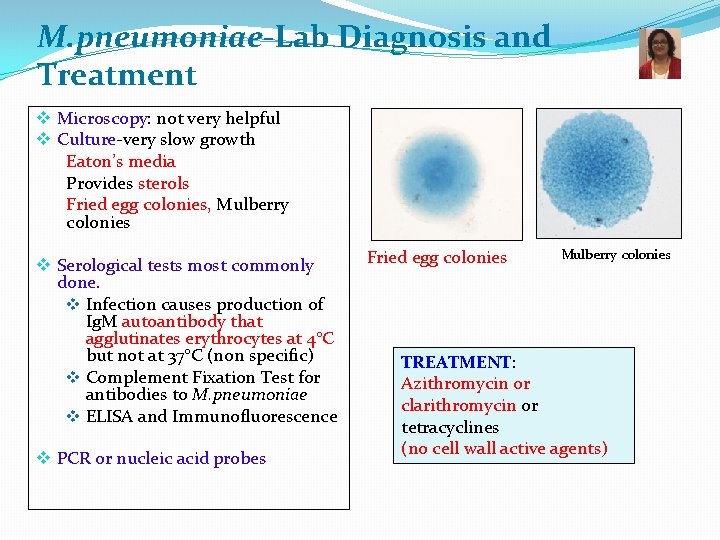

M. pneumoniae-Lab Diagnosis and Treatment v Microscopy: not very helpful v Culture-very slow growth Eaton’s media Provides sterols Fried egg colonies, Mulberry colonies v Serological tests most commonly done. v Infection causes production of Ig. M autoantibody that agglutinates erythrocytes at 4°C but not at 37°C (non specific) v Complement Fixation Test for antibodies to M. pneumoniae v ELISA and Immunofluorescence v PCR or nucleic acid probes Fried egg colonies Mulberry colonies TREATMENT: Azithromycin or clarithromycin or tetracyclines (no cell wall active agents)